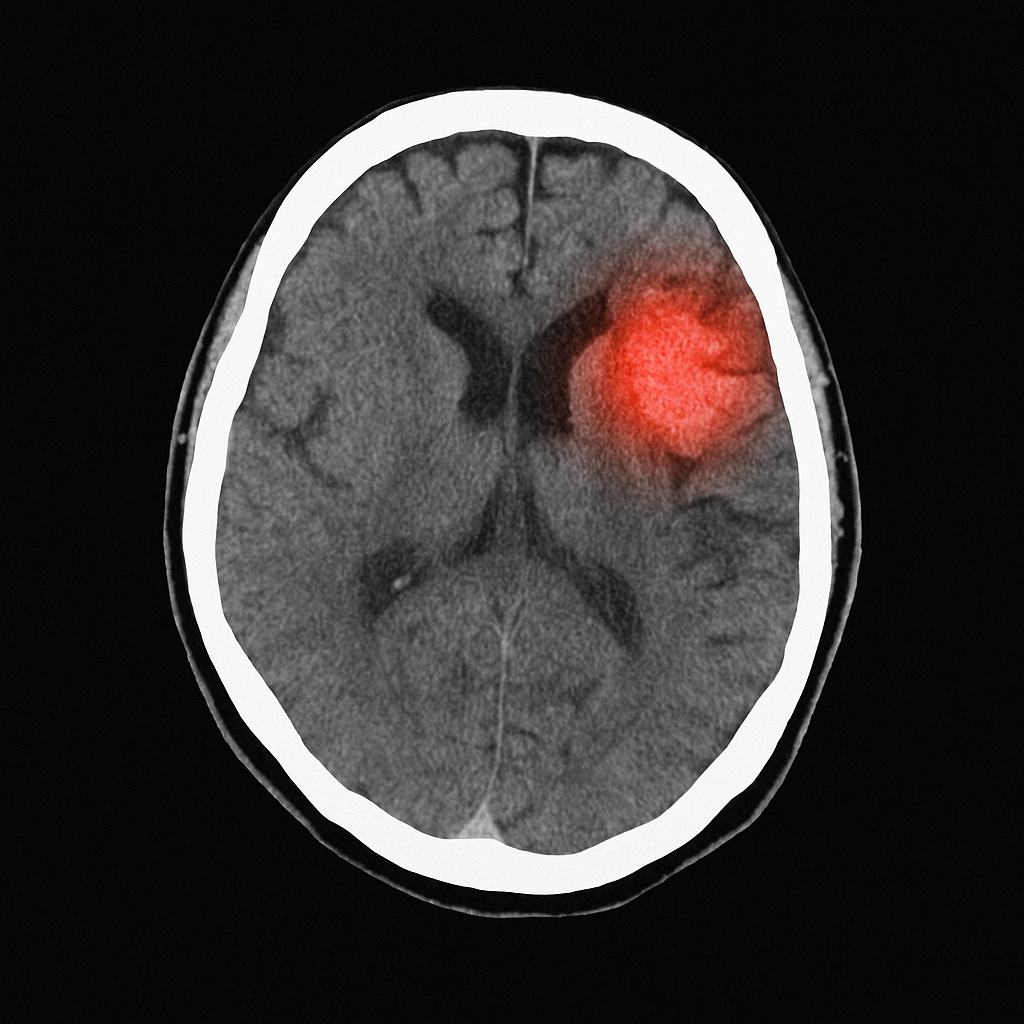

Diante de qualquer suspeita, deve-se procurar atendimento de emergência imediatamente. Exames de imagem como a tomografia computadorizada ou a ressonância magnética ajudam a confirmar o diagnóstico. O tratamento dependerá do tipo de AVC, mas pode incluir: